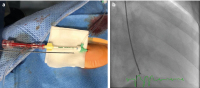

Abbildung 2a-b: (a): Myokardbiopsie über die rechte Arteria radialis mit einer 6F-Radialisschleuse (RAIN Sheath™ Transradial Introducer, Cordis). (b): Angiographisches Bild (RAO 30) der radialen links­ventrikulären Myokardbiopsie mit einem rechten Judkins-Führungs­katheter (ADROIT ™ Guiding Catheter, Cordis, ID.072‘‘) mit einem 5.5F Bioptom (Biopsy Forceps, Cordis).

Keywords: FotoKardiologieKoronarangiographieMyokardbiopsie